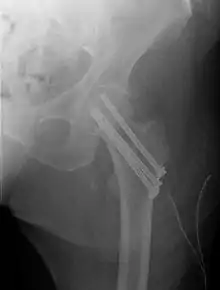

| Intertrochanteric hip fracture in a 17-year-old male | |

Closed reduction may not be satisfactory and open reduction then becomes necessary.[38] The use of open reduction has been reported as 8-13% among pertrochanteric fractures, and 52% among intertrochanteric fractures.[39] Both intertrochanteric and pertrochanteric fractures may be treated by a dynamic hip screw and plate, or an intramedullary rod.[38]

The fracture typically takes 3–6 months to heal. As it is only common in elderly, removal of the dynamic hip screw is usually not recommended to avoid unnecessary risk of second operation and the increased risk of re-fracture after implant removal. The most common cause for hip fractures in the elderly is osteoporosis; if this is the case, treatment of the osteoporosis can well reduce the risk of further fracture. Only young patients tend to consider having it removed; the implant may function as a stress riser, increasing the risk of a break if another accident occurs.